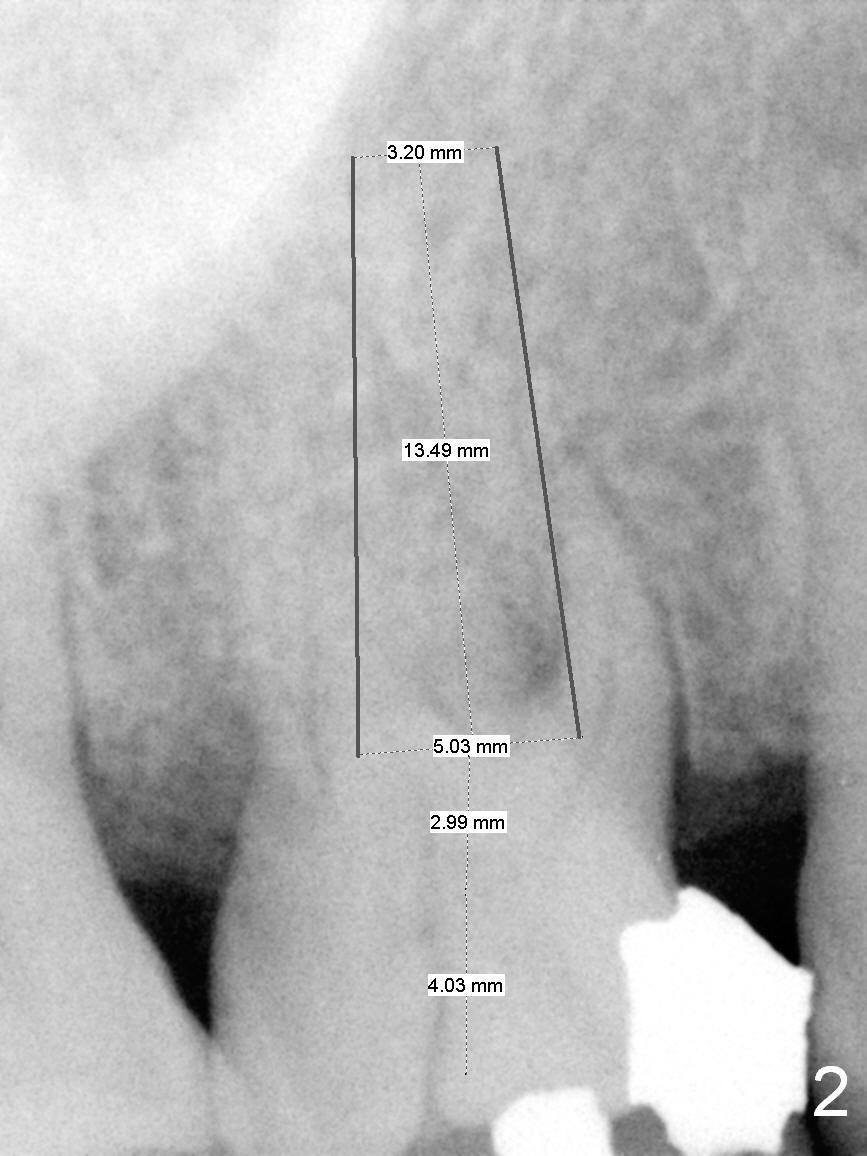

![]() UF Immediate Implant for Upper 1st Molar A 52-year-old lady has chewed on the right side for several years, because of loss #14. The mesiolingual cusp of the tooth #3 fractures subgingivaly (Fig.1 <). The tooth has trifurcated roots. Surgical handpiece may be used for sectioning if simple extraction with proximators is not feasible. After extraction, granulation tissue may be present in the palatal wall, next to the crack line. If the defect is large, use Osteotape for repair before bone graft. The socket will be packed with Metronidazole 2% Xylocaine 1:50,000 Epinephrine for 3 times. Osteotomy is initiated in the middle of the septum using UF cassette drills until 1 size smaller than the implant planned (Fig.2). If the implant is placed in the middle of the edentulous space, a cemented abutment as large as 7.5x4(3) mm is placed. Return to Upper Molar Immediate Implant Xin Wei, DDS, PhD, MS 1st edition 09/19/2015, last revision 01/19/2019 |